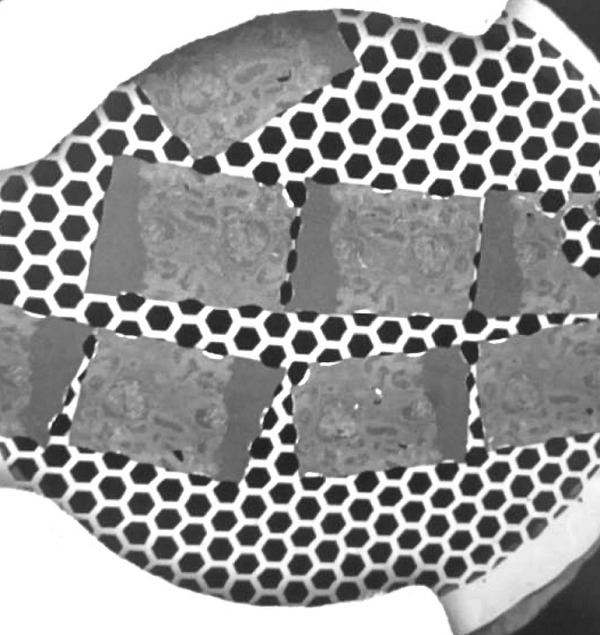

图1. 高通量全自动病理切片电子成像仪

项目从医院病理科电镜病理检测存在的仪器维护成本高、操作复杂、通量低、人力成本高等痛点出发,成功研制了针对病理组织切片样品的高通量扫描透射电子显微镜SmartView(图1),发明了载网托盘和新型的装载方式(图2),一次可以装载500个病理切片载网,实现了8K*8K的高速扫描透射成像能力,仪器成像分辨率优于1.1nm,可以进行病理组织切片样品高速和高质量成像(图3,图4),将有效推动生物医学病理电镜检测快速发展。